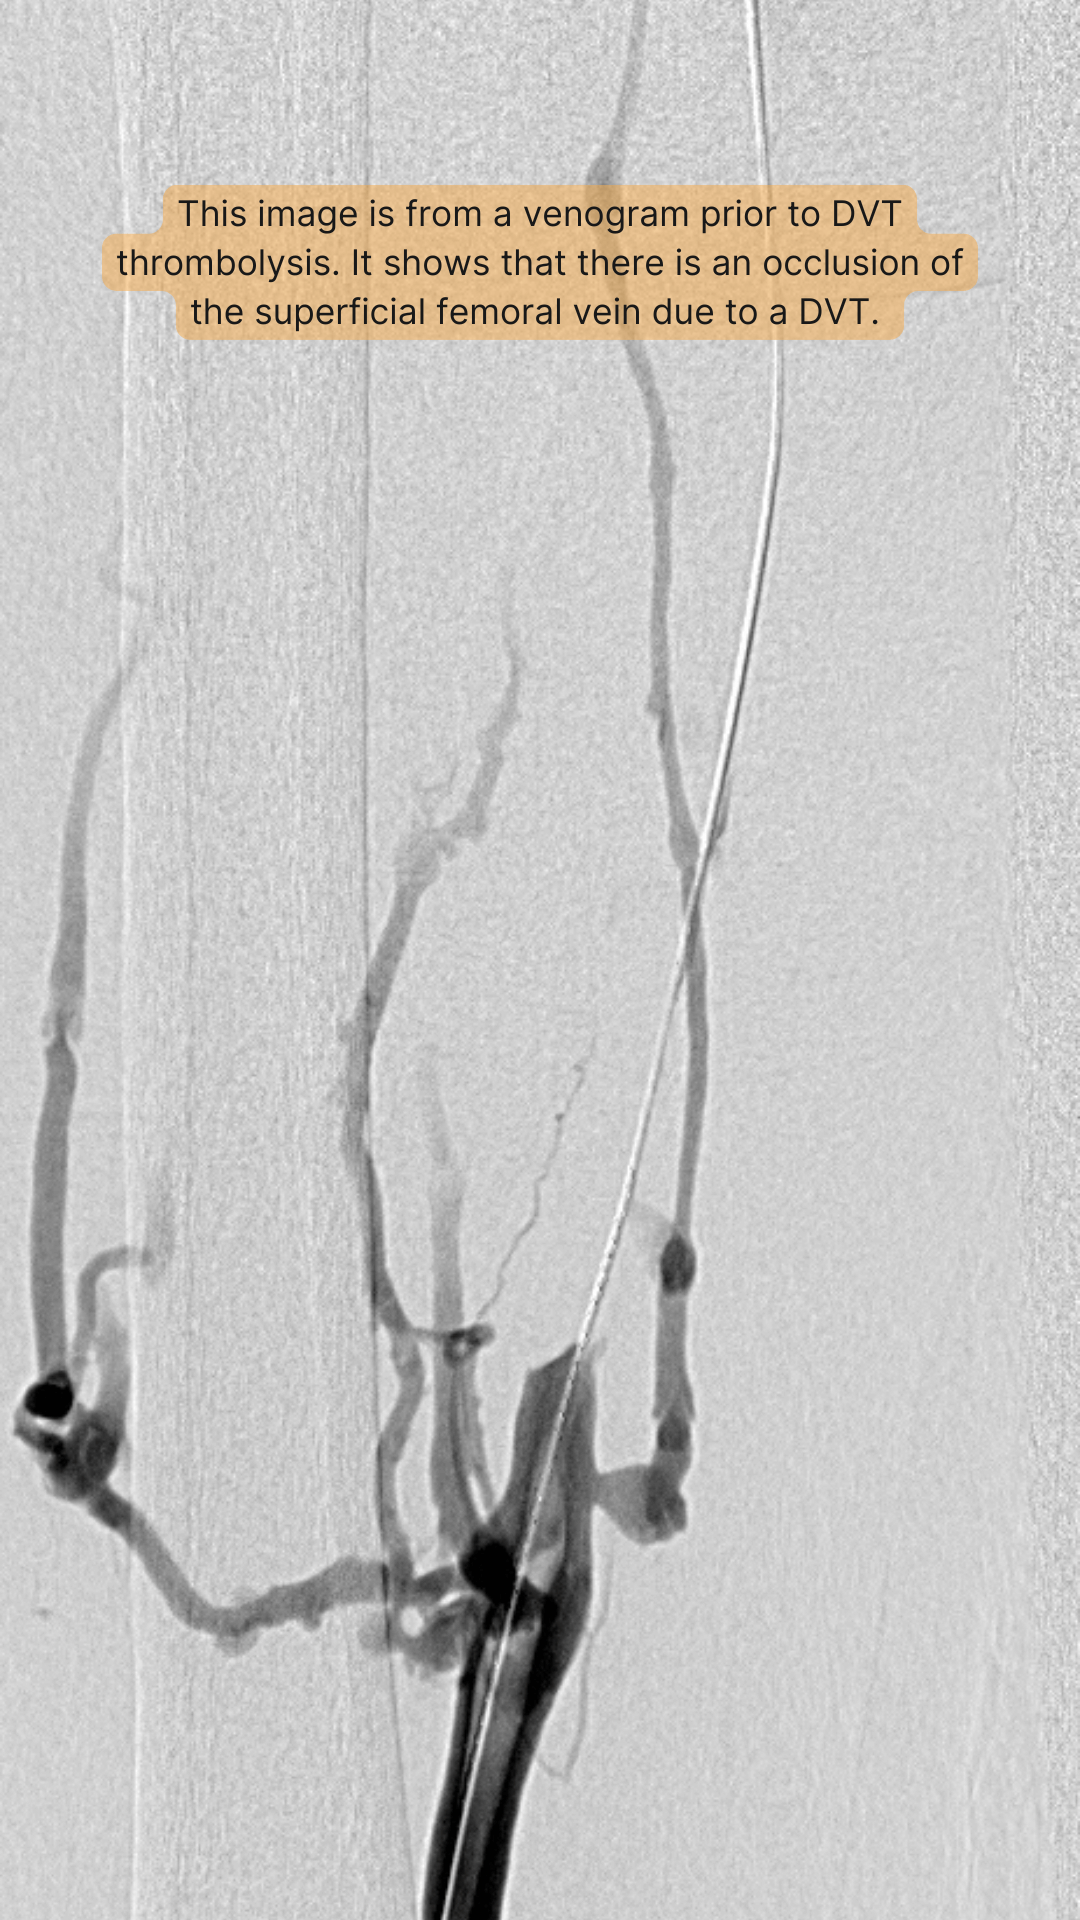

When a DVT is suspected, an ultrasound is typically the first test that is performed. This is a painless test that usually takes less than 30 minutes to perform. During this test, the sonographer places the ultrasound transducer on the leg and images the veins of the leg from the groin to the calf. It is possible to directly visualize blood flow and clot within a leg vein using ultrasound. Historically, a test known as a venogram was used for a diagnosing a DVT, but this has been essentially replaced with ultrasound. Today, venography is reserved for patients who have difficulty undergoing an ultrasound examination (usually due to large legs) or who have had an ultrasound examination that was unable to definitely conclude if a DVT is present. An interventional radiologist performs this test. It involves placing a small needle into a vein in the foot and then injecting an x-ray dye into the veins. This enables the veins to be directly observed with x-rays, which typically allows for a definitive diagnosis of DVT to be made.

Catheter-directed thrombolysis is performed by an interventional radiologist and is best performed as soon as possible after a DVT is diagnosed. Prior to the procedure, some patients may receive a CT scan of the head to make sure that there is not an increased risk for bleeding. During this procedure, a small catheter (tube) is placed directly into the affected vein, usually from behind the knee. Once the catheter is in place, a drug can be administered directly into the clot in order to dissolve the clot. New devices are now available which can disrupt the clot in order to facilitate delivery of the drug directly into the thrombus. These devices also allow for the removal of the clot through the catheter. By removing the clot, it is hoped there will be less damage to the vein and therefore fewer symptoms associated with a post-thrombotic syndrome. Once the clot is dissolved and/or removed, it may be possible to see if there is any narrowing within the vein. This can subsequently be treated with angioplasty or placement of a stent within the narrowed vein. Often patients need to spend the night in the intensive care unit (ICU) while the drug to dissolve clot is being given.